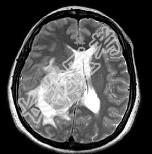

- 单项选择题女,45岁, 右眼视力下降8个月,右颜面麻木半个月, 时有头昏,味觉减退, 请根据所提供图像,选择最可能的诊断是 ( )

A、(右侧脑室)胶质瘤

B、(右侧脑室)脉络膜乳头状瘤

C、(右侧脑室)转移瘤

D、(右侧脑室)室管膜瘤

E、(右侧脑室)脑膜瘤(合体细胞型)